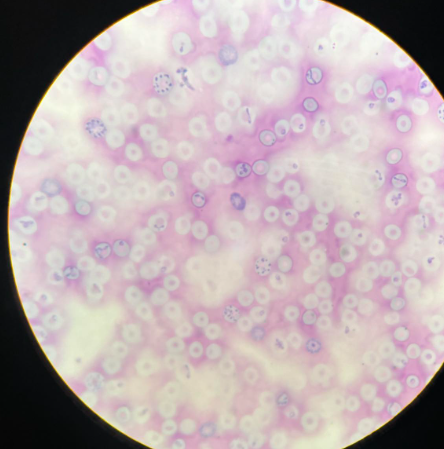

plasmodium falciparum stadia schizogonii krwinkowej

plasmodium falciparum stadia schizogonii krwinkowej